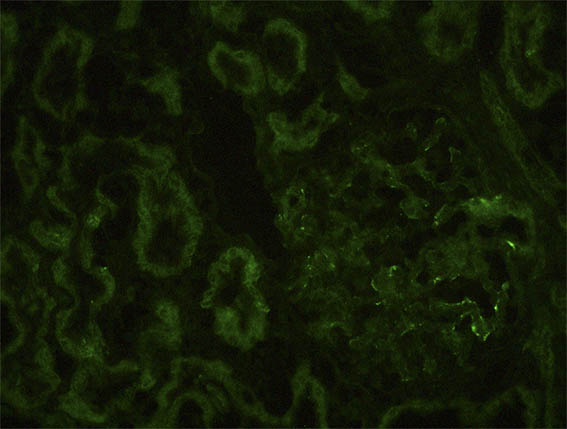

Figura 11. Inmunofluorescencia directa para IgM, X400.

Figura 12. Inmunofluorescencia indirecta para la cadena alfa-1 (MAB1) del colágeno tipo IV, X400.

Figura 13. Inmunofluorescencia indirecta para la cadena alfa-3 (MAB3) del colágeno tipo IV, X400.

Figura 14. Inmunofluorescencia indirecta para la cadena alfa-5 (MAB5) del colágeno tipo IV, X400.

Figura 15. Control positivo (en riñón normal) para cadenas alfa-3 (MAB3 - izquierda) y alfa-5 (MAB5 - derecha) del colágeno tipo IV, X400.

Inmunofluorescencia para IgA, IgG, C3 y C1q: Negativas.